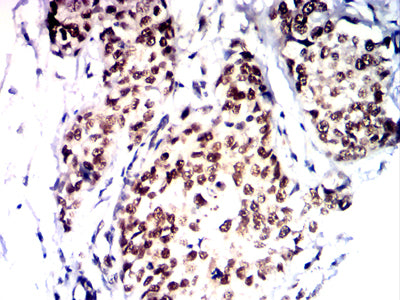

Immunohistochemical analysis of paraffin-embedded human bladder cancer tissues using PMS2 mouse mAb with DAB staining.